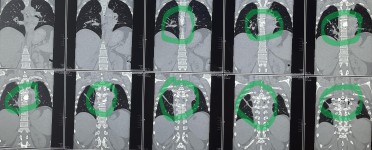

43-year-old female patient suffers from increasing weakness in the lower extremities